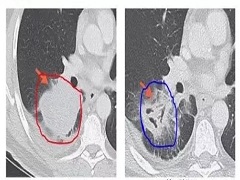

自2014年9月以来,PD-1抑制剂已经被美国FDA正式批准用于:恶性黑色素瘤、非小细胞肺癌、肝癌、胃癌、肾癌、膀胱癌、头颈部肿瘤、霍奇金淋巴瘤、Merkel细胞癌以及所有微卫星高度不稳定(MSI-H)的实体瘤。

此外,PD-1抑制剂在结直肠癌、食管癌、三阴性乳腺癌、鼻咽癌、卵巢癌、宫颈癌、前列腺癌、子宫内膜癌、胶质瘤、神经内分泌肿瘤、恶性间皮瘤、非霍奇金淋巴瘤等其他多种实体瘤中,显示出了初步的、鼓舞人心的疗效。